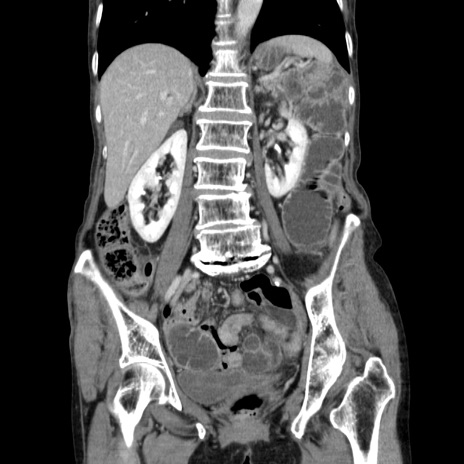

症例25(冠状断像)

【症例】80歳代女性

【主訴】胸のつかえ感

【現病歴】約9時間前に食後から胸のつかえた感じあり、嘔吐あり、来院。

【既往歴】胃癌(全摘)、胆摘、虫垂炎

【身体所見】心窩部に圧痛あり、反跳痛なし。

【データ】WBC 5700、CRP 0.05